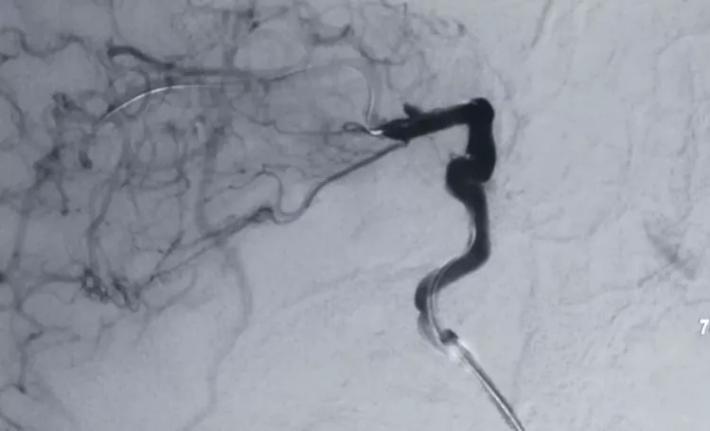

5FNavien导引管输送Willis到位。

释放支架后见BBA显影变浅,仅后半部分晚期显影,脉前A显影好,再次后扩。

二次后扩后颈内动脉造影见BBA逆向充盈部分显影,晚期仍有造影剂滞留,如远端再次叠套一支架必会累及脉前A,2周后复查DsA吧,希望BBA不破而且血栓自愈。

二次复合手术中DsA,黄箭→BBA,白箭→M1,绿箭→STA,M1由于痉挛与STA管径相当,病人有部分开放的前交通,所以本例我们采取的策略是①单支STA一M2搭桥②ICA颅外段阻断③BBA包裏夹闭or孤立④如包裏夹闭失败行孤立术则行STA一M2双支搭桥。